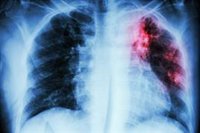

Archivo - Imagen de recurso de un cribado.

Archivo - Imagen de recurso de un cribado. - ISAYILDIZ/ISTOCK - Archivo